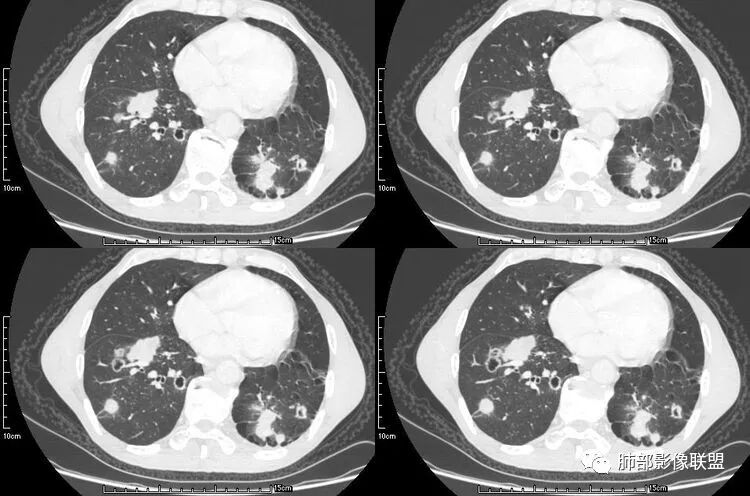

患者老年男性,咳嗽、咳痰、痰中带血伴胸闷2月余。长期大量吸烟史。查肝肾功能、血糖、血脂、心肌酶、电解质、血沉、C反应蛋白、抗“O”、类风湿因子、抗核抗体谱无明显异常。肿瘤标志物提示NSE、CYFRA21-1稍升高。胸部CT:肺气肿背景,左肺下叶后基底段不规则肿块影,见支气管截断,内见大片状低密度区及部分血管影,增强轻度强化,远端空洞形成。双肺多发不规则实性结节影、见毛刺、胸膜牵拉及血管集束,结节内见空洞形成,部分可见血管影,多位于胸膜下。双肺见多发肺大泡。综合考虑左下肺恶性病变并双肺转移。鳞癌或淋巴瘤可能。鉴别血管炎性病变及真菌感染。

本病例左肺下叶肿块,有深分叶、毛刺、胸膜牵拉凹陷、支气管截断及纵隔内淋巴结肿大等征象,都均支持病灶为恶性,如腺癌,而且叶间裂的多发结节也提示是腺癌来源可能大;双肺多发结节、肿块,大部分病灶有分叶、毛刺及胸膜凹陷的恶性征象,与原发肿瘤本身的性质有关,所以应该与左肺下叶肿块同源,而且双肺多发病灶内空洞也具有多样性;

此病例中空洞形态多样,内壁不光整,有分隔影,周围未见明显卫星灶及钙化灶,结核不太符合;患者病史慢性病史,无明显发热,缺乏中毒临床表现,急性感染基本排除;各种中性粒细胞胞浆抗体阴性,没有鼻窦炎,肾脏等病史,基本排除血管炎;霉菌性空洞常见于免疫机能低下者, 常为空洞、肺炎、伴“ 晕圈”征的结节及支气管扩张合并存在。